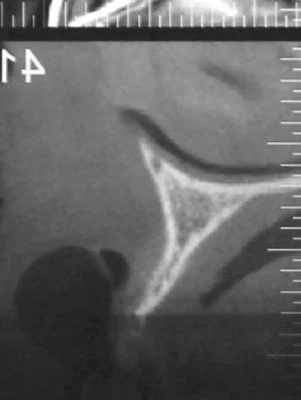

術前のCT画像。インプラントを入れられないくらい骨が痩せてしまっているためブロック骨移植によって骨の厚みを増やしてからインプラントの埋入をおこなうことになりました。

術前術後のCT画像。外側に骨のボリュームが増えているのがわかります。